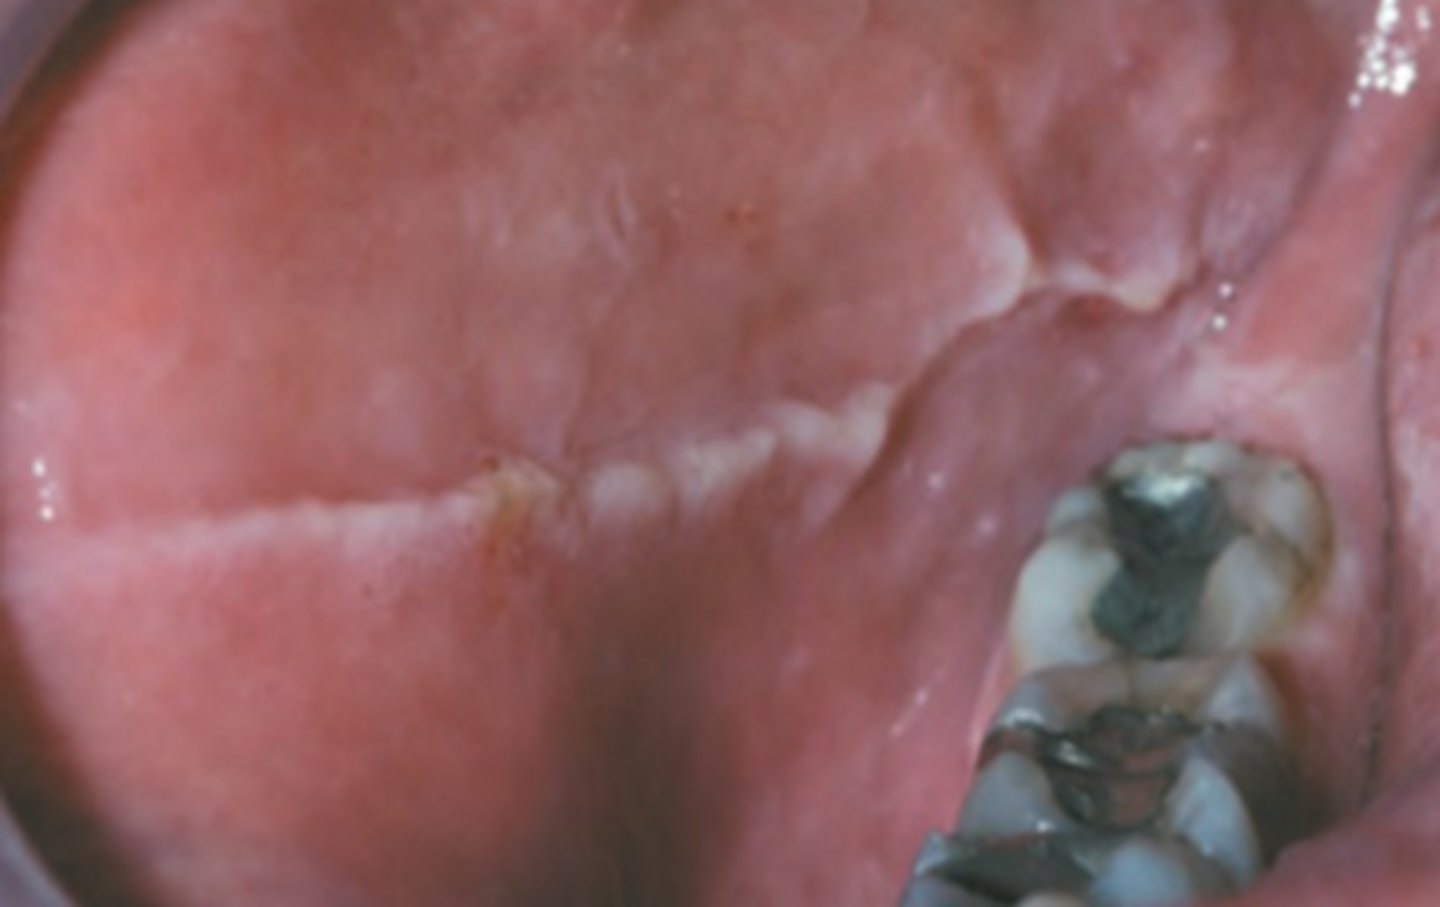

What is tobacco pouch keratosis?

corrugated/wrinkled vestibule

⢠smokeless tobacco use

⢠biopsy if ulcerated or doesn't heal in 14 days after movement of tobacco